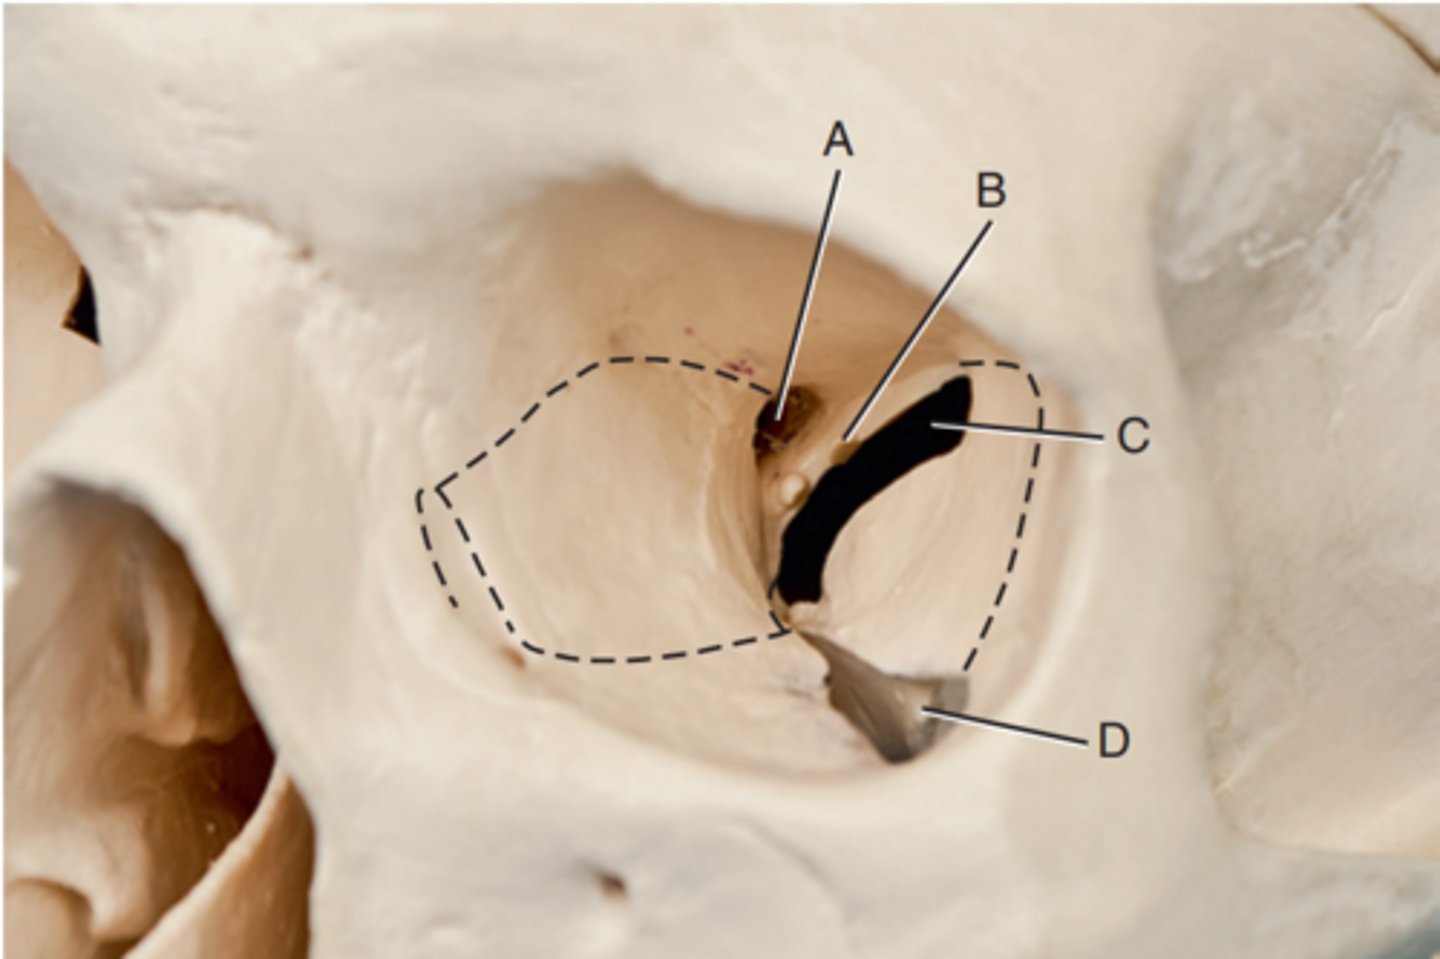

Optic foramen

Label A

Sphenoid strut

Label B

Superior orbital fissure

Label C

Inferior orbital fissure

Label D

Orbital plate of frontal bone

Label A

Sphenoid bone

Label B

Optic foramen and canal

Label C

Superior orbital fissure

Label D

Infraorbital margin (IOM)

Label E

Sphenoid strut

Label F

Lateral orbital margin

Label G

Supraorbital margin

Label H